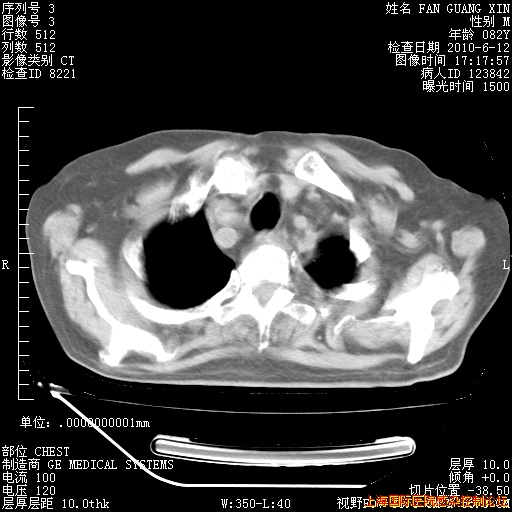

补发6月12日肺部CT肺窗

6月12日肺窗

6月12日纵膈窗